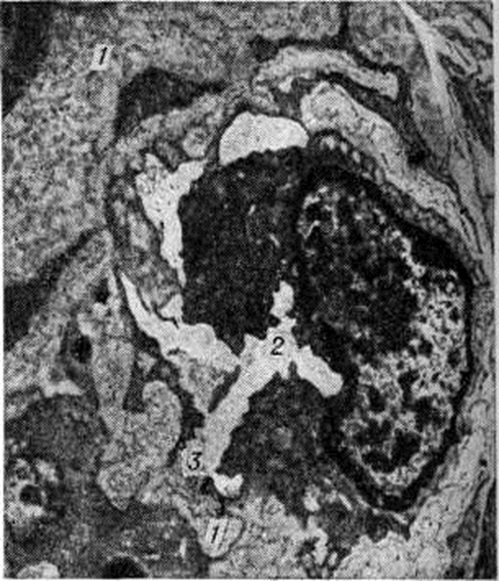

Гиалиноз относится к внеклеточным (мезенхимальным) диспротеинозам. Появление в цитоплазме гиалиновых капель (гиалиново-капельная дистрофия) или шаров (гиалиновые шары) не связано с Гиалиноз. Гиалин является фибриллярным белком (рисунок 1), в построении которого принимают участие плазменные белки, в частности фибрин. При иммуно-гистохимические исследовании в гиалине обнаруживают не только фибрин, но и компоненты иммунных комплексов (иммунные глобулины, фракции комплемента). Гиалиновые массы стойки к действию кислот, щелочей, ферментов, хорошо окрашиваются кислыми красками (эозин, кислый фуксин), пикрофуксином красятся в жёлтый или красный цвет; в массах гиалина могут откладываться липиды, соли кальция. Внешний вид органов и тканей при Гиалиноз зависит от стадии процесса; чаще Гиалиноз ничем не проявляется и обнаруживается лишь при микроскопическом исследовании. В тех случаях, когда процесс выражен резко, ткани становятся бледными, плотными, полупрозрачными. Гиалиноз, в частности артериол, может привести к деформации и сморщиванию органов (например, развитие артериолосклеротического нефроцирроза, клапанного порока сердца).

Гиалиноз наблюдается в соединительной ткани, строме органов и стенке сосудов (рисунок 2) в исходе плазматического пропитывания, фибриноидного набухания, склероза, хронический воспаления, некроза. В исходе плазматического пропитывания возникает Гиалиноз сосудов, чаще в артериальной системе. Наиболее распространён Гиалиноз мелких артерий и артериол (смотри Артериолосклероз). Гиалиноз артериол возникает в результате повреждения эндотелия, аргирофильных мембран и гладкомышечных волокон и пропитывания стенок сосуда белками плазмы крови, которые затем подвергаются ферментативным воздействиям, коагулируются и уплотняются, превращаясь в гиалиноподобное плотное вещество. Гиалиновые массы оттесняют кнаружи и разрушают эластическую пластинку, что ведёт к истончению средней оболочки; в результате артериолы превращаются в утолщённые плотные трубочки с резко суженным или полностью закрытым просветом. Гиалиноз мелких артерий и артериол, носящий системный характер, но наиболее выраженный в почках (рисунок 3 и 4), головном мозге, сетчатке глаза, поджелудочной железе, коже (рисунок 5), особенно характерен для гипертонической болезни (гипертонический артериологиалиноз). Нередко системный Гиалиноз артериол и мелких артерий наблюдается при хронический васкулярном гломерулонефрите и симптоматической артериальной гипертензии любого генеза. Распространённый Гиалиноз артерий эластического и эластическо-мышечного типов постоянно наблюдается при атеросклерозе, диабете и отражает процессы плазморрагии и инсудации, характерные для этих заболеваний. Местный Гиалиноз артерий как физиологическое явление встречается в селезёнке взрослых и пожилых людей, отражая функционально-морфологически особенности селезёнки как органа депонирования крови.